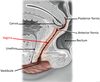

Green arrow?

Postganglionic sympathetic fibers (they synapsed in the ganglion) leaving the sympathetic chain and joining a sacral nerve (S1). Will leave the pelvis with to go to the legs to nnervates blood vessels, sweat glands, hair follicules, etc.

Red arrow?

Sacral splanchnic nerves - Preganglionic sympathetic fibers (they came down the chain) which will synapse in the inferior hypogastric plexus. They provide sympathetic innervation to the pelvic organs.